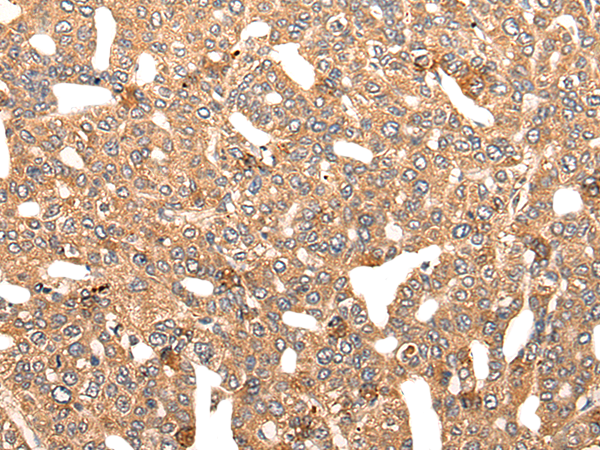

IHC positive control: |

Human colorectal cancer and human lung cancer |

IHC Recommend dilution: |

20-100 |